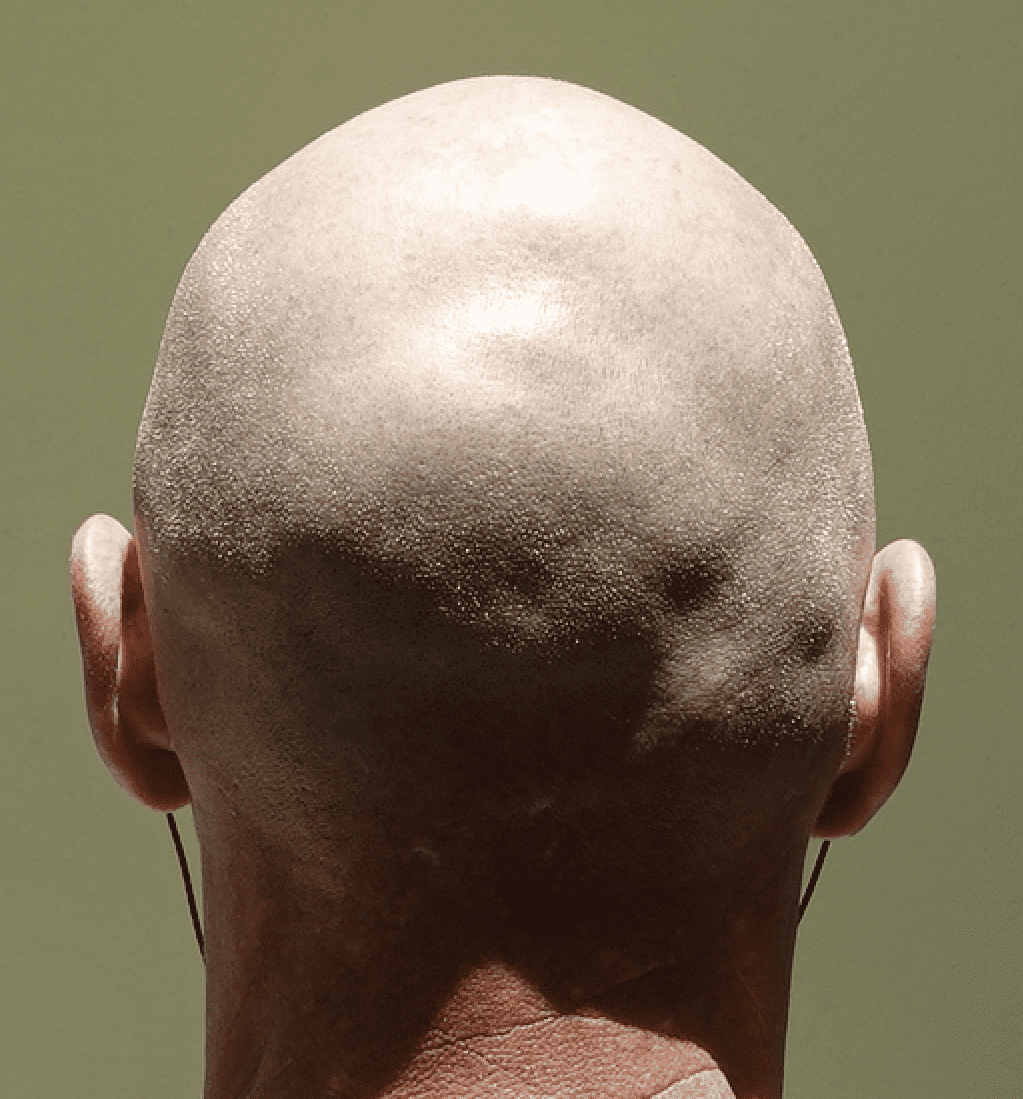

Desire for less prominent protrusion on the back of the head.

Occipital skull reduction through a bone burring technique.

Desire for less prominent protrusion on the back of the head.

Occipital skull reduction through a bone burring technique.